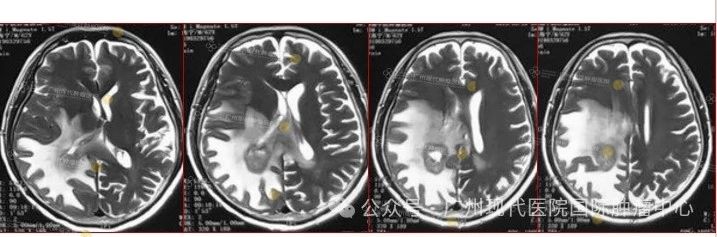

患者:63歲,男性

2013-11,體檢發(fā)現(xiàn)肺部腫瘤,

2015-11,頭顱MR檢查提示顱內(nèi)轉(zhuǎn)移

2018-11,顱內(nèi)腫瘤進(jìn)展,無(wú)法接受后續(xù)治療

2019-3,接受腦瘤粒子植入術(shù)

2019-7,顱內(nèi)腫瘤基本消失,正常生活至今

2019年7月,顱內(nèi)腫瘤已基本消失